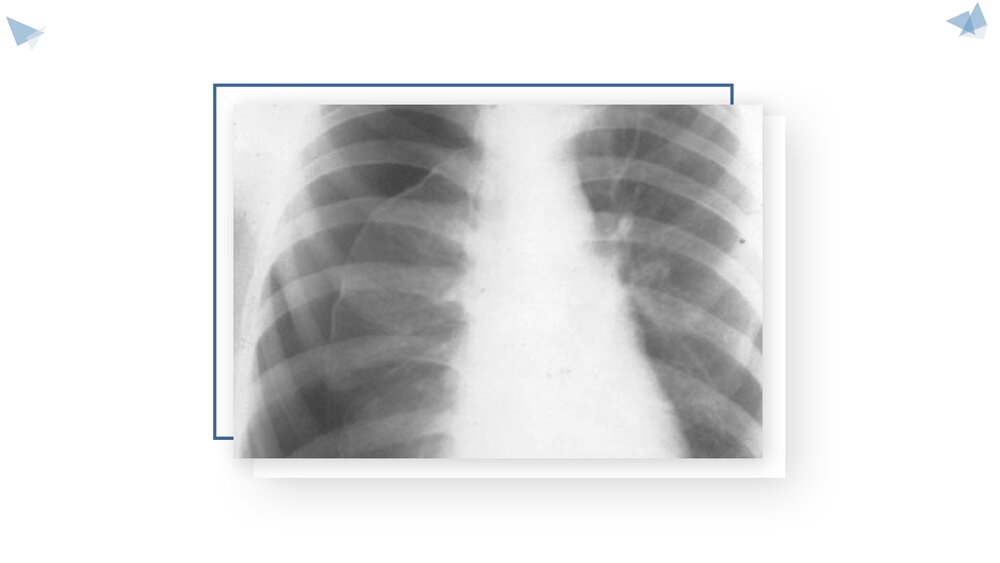

气胸的护理查房汇报人:xxx基本概念 肺无明显病变由胸膜下气肿泡破裂形成者称特发性气胸;继发于慢阻肺肺结核等胸膜及肺疾病者称继发性气胸.按病理生理变化又分为闭合性(单纯性)、开放性(交通性)和张力性(高压性)三类病因:1.外伤气胸2.继发性气胸3.特发性气胸4.慢性气胸5.创伤性气胸临床类型类型:1.闭合性气胸(单纯性)  2.张力性气胸(高压性)3.开放性气胸(交通性)单纯性张力性气胸临床表现张力性气胸由于胸腔内压骤然升高,肺被压缩,纵隔移位,出现严重呼吸循环障碍,病人表情紧张、胸闷、甚至有心律失常,常挣扎坐起,烦躁不安,有紫绀、冷汗、脉快、虚脱、甚至有呼吸衰竭、意识不清。02患者常有持重物、屏气、剧烈运动等诱发因素,但也有在睡眠中发生气胸者,病人突感一侧胸痛、气急、憋气,可有...